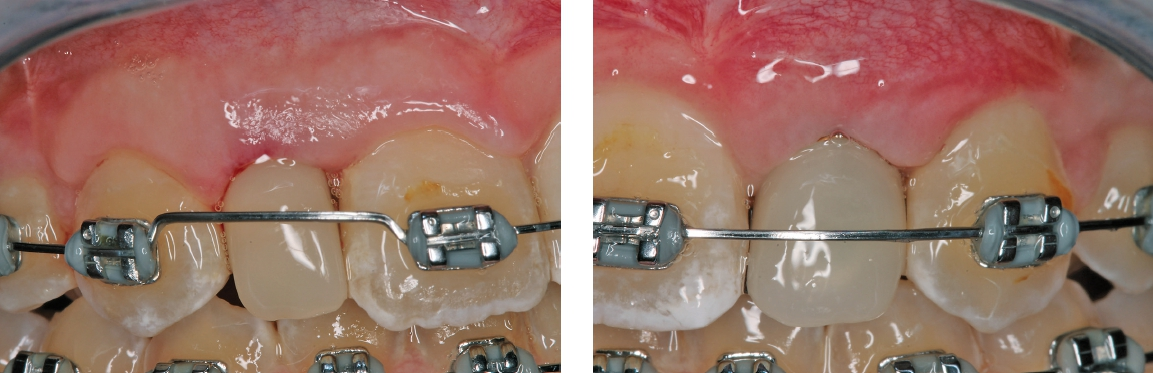

Eine 17-jährige Patientin wurde an unsere Praxis mit dem Wunsch nach einer festsitzenden implantatprothetischen Versorgung der lateralen Schneidezähne 12 und 22 überwiesen. Nach entsprechender Aufklärung und intensiver Beratung wurde zunächst ein DVT erstellt, um das genaue Ausmaß der dreidimensionalen Knochenresorption in regio der fehlenden lateralen Schneidezähne regio 12 und 22 beurteilen zu können. Die röntgenlogische Auswertung ergab eine hochgradige horizontale Alveolarfortsatzbreite von knapp 3 mm in regio 12 respektive von knapp 2,5 mm in regio 22 mit stark ausgeprägter konkaver Kontur der bukkalen Lamelle (Abb. 1). Allein das klinische Bild (Abb. 2 und 3) zeigte eine ausgeprägte horizontale Alveolarfortsatzatrophie in regio 12 und 22 mit ausgeprägten Konkavitäten in der bukkalen Lamelle.

Zunächst wurde ein intensives Beratungsgespräch mit dem behandelnden Kieferorthopäden durchgeführt, wo die Patientin aufgrund eines seitlich offenen Bisses und zur Etablierung einer eugnathen Okklusion mit Hilfe einer MB-Technik bereits in Behandlung war. Die kieferorthopädische Auswertung ergab ein mesiofaziales Wachstum mit dolichofazialer Tendenz. Bei diesem Wachstumstyp entwickelt sich das Mittelgesicht bei den Adoleszenten nach kausal und vestibulär, wobei die hier dolichofaziale Wachstumstendenz eher ein schmales Gesicht mit höher Gesichtshöhe ausbildet.